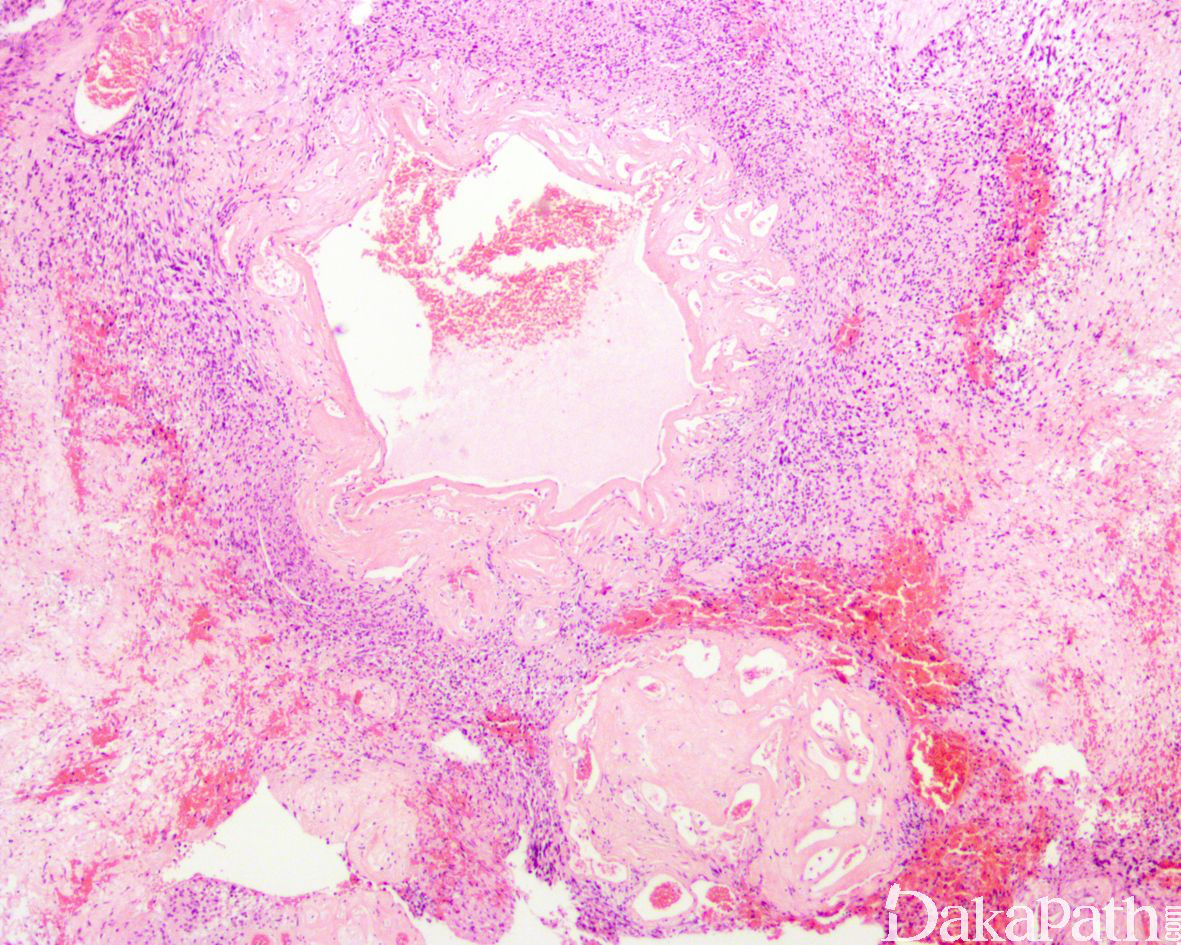

- 退行性改变主要表现为囊性变、钙化、陈旧性出血及机化、间质内或血管周围广泛而明显的透明样变性等;

- 肿瘤内常见大量吞噬含铁血黄素的组织细胞;

- 多数病例可见一些退变的核大深染的畸形瘤细胞,核常呈分叶状,可见核内包涵体;